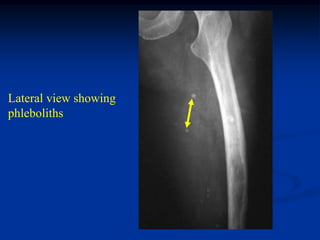

Case #585

36 year female with

Muffucci’s syndrome

Lateral view showing

phleboliths

Opposite femur

Lateral view with

hemangioma

enchondroma